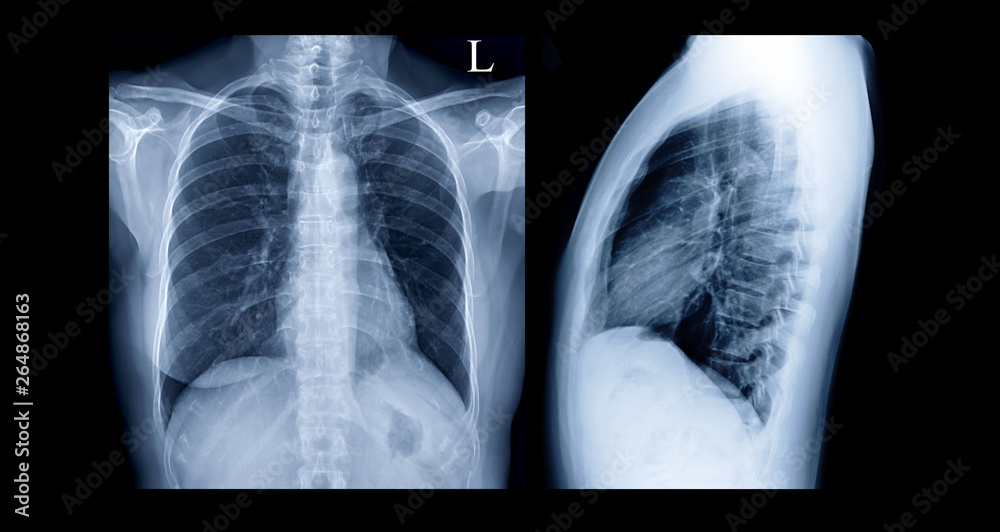

Comparison of Chest Xray PA and Lateral view or XRay Image Of Human Chest X Ray Pa And Lateral Interpretation Only Two Views Pa and lateral views of the chest; This section lists what the radiologist saw in each area of the. The interpretation of a chest film. Ap portable view of the chest; 71046, 71045 (two views (pa & lat) of chest. The most complete or best x ray for diagnosis is the one with 2 views. Pa as above and lateral. Chest X Ray Pa And Lateral Interpretation Only Two Views.